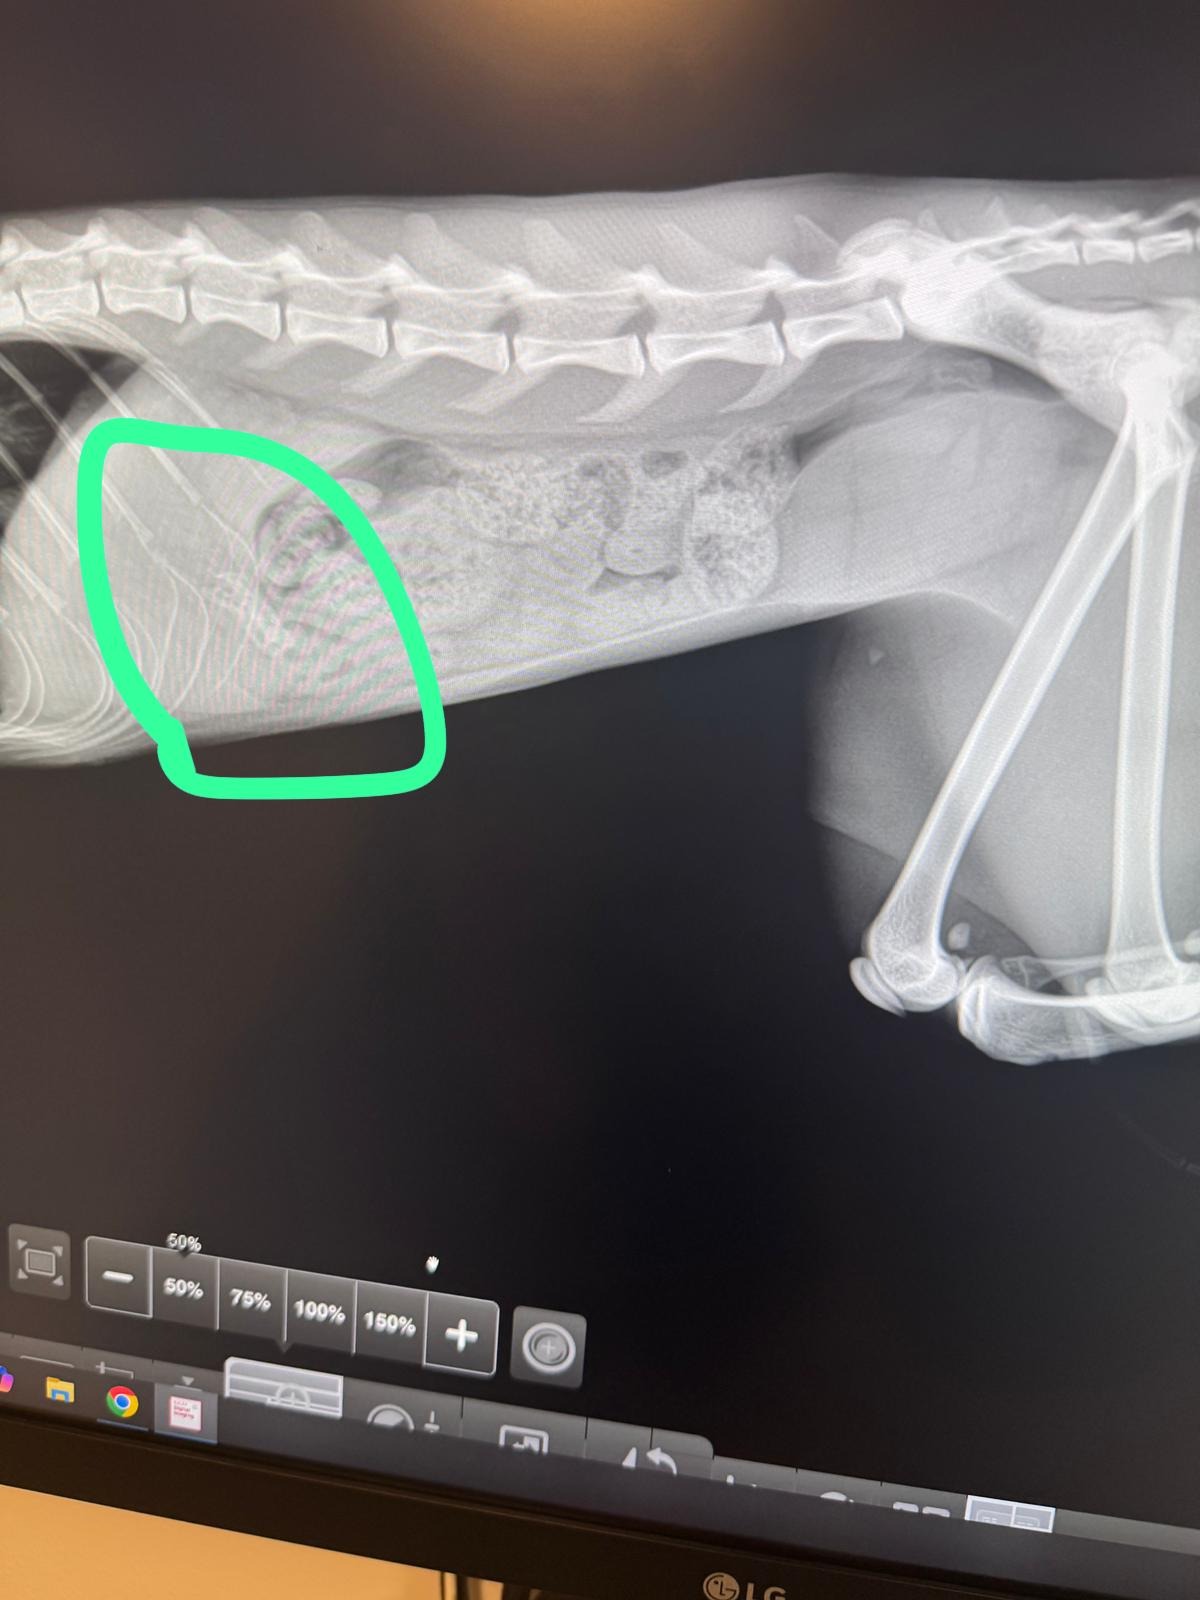

My sweet cat, Suki, recently swallowed a small piece of metal that is now causing serious damage to her stomach. She is in a lot of pain, and the vets have told me that she urgently needs a delicate surgery to save her life.

Mi gatita Suki se tragó accidentalmente un pedazo de metal que está lacerando su estómago. Está sufriendo mucho, y los veterinarios me han dicho que necesita una cirugía delicada y urgente para salvarle la vida.